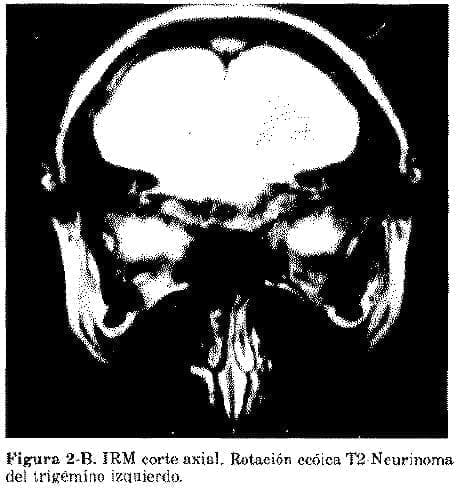

Hasta el momento ha sido necesario enviar a los Estados Unidos y al Canadá, varios enfermos que requerían diagnóstico de Iconografía por Resonancia Magnética. En un caso se trata de una profesional joven con un tumor del nervio trigémino no demostrado en la escanografía; el iconograma fue definitivo para hacer el diagnóstico e intervenir a la enferma con buenos resultados.